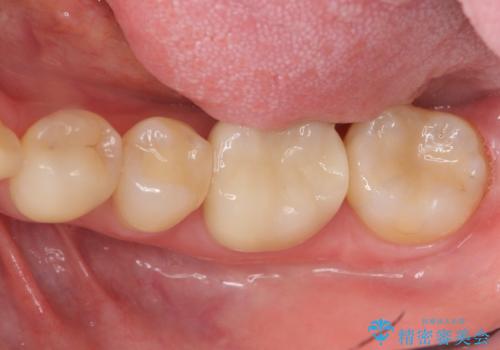

治療後、銀歯と虫歯のない清潔な口腔内環境を達成することができました。

目立つ銀歯をセラミックへ